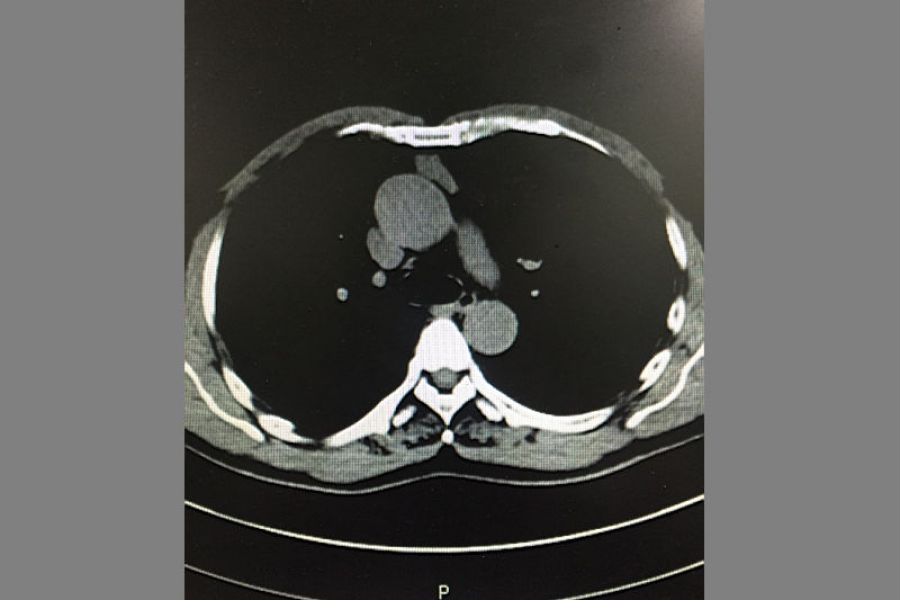

患者王某某40岁,因右胸阵发性疼痛1年入住我院疼痛科,检查发现前上纵膈肿瘤。经心胸外科钟强主治医师会诊后转入心胸外科。转入后予积极完善相关检查,排除相关禁忌症,考虑患者年轻,对创伤小、美观等要求,经研究决定予行胸腔手术。手术入路选择经剑突下切口,黄勇科主任及向加树副主任临场指导,术中杨智杰副主任医师、张建军主治医师及左选健住院医师密切配合,仔细解剖,历经2小时手术完整切除肿瘤。术后患者无明显并发症,主诉疼痛感轻,恢复良好。

纵膈肿瘤影像学表现